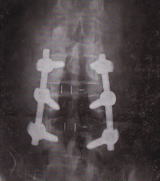

当鍼灸院で手術後の体調不良で多い症状は、脊椎術後疼痛症候群(FSBB)で脊椎の手術をした後も、腰や下肢に痛みやしびれが残ってしまう症状です。

これは疾患名ではなく、病態を指す言葉として使われていて、ボルトなどを入れて脊椎を固定する手術で40%前後と推定されています。